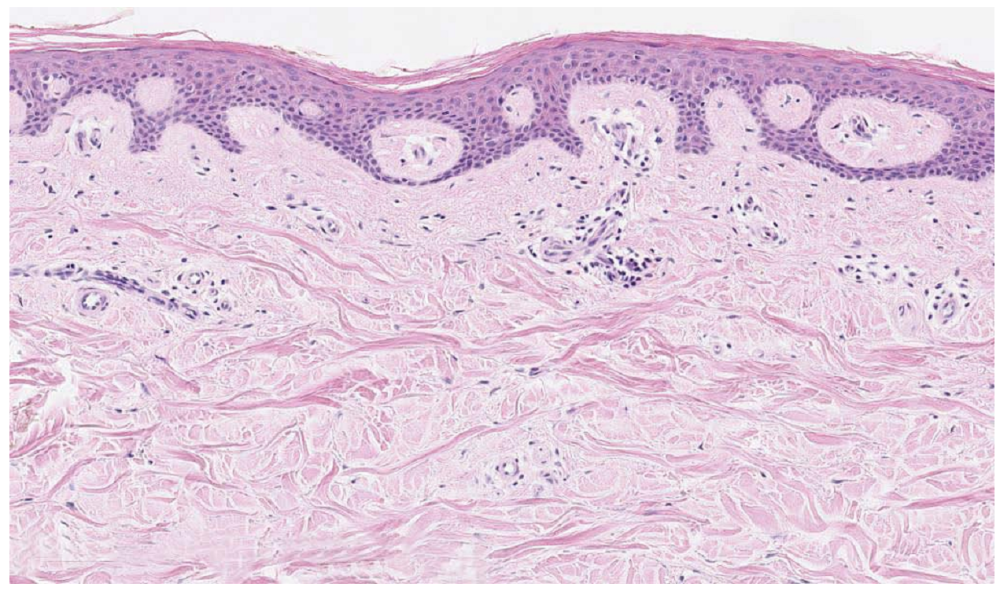

胶原纤维(真皮里的“迷雾”):它们就像是大雾天气里的密集水滴。激光射入真皮层时,主要就是被这些纤维给撞散的。

图片

真皮层粗大的胶原纤维

当皮肤老化时,胶原纤维断裂、排列紊乱,更容易对进入真皮的激光与光产生散射。